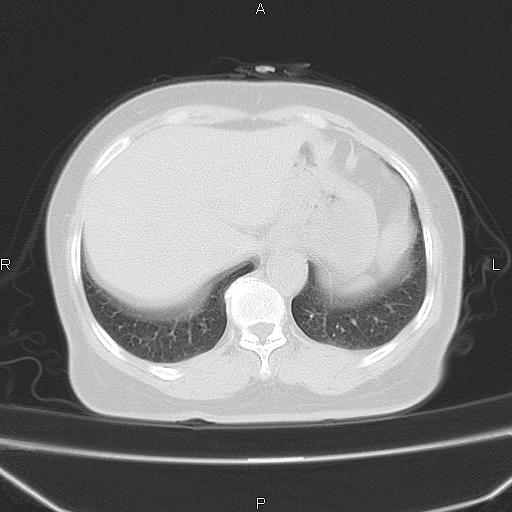

胸腺瘤

女、63Y 双眼睑下垂,早轻晚重。 胸腺瘤???

结果胸腺瘤